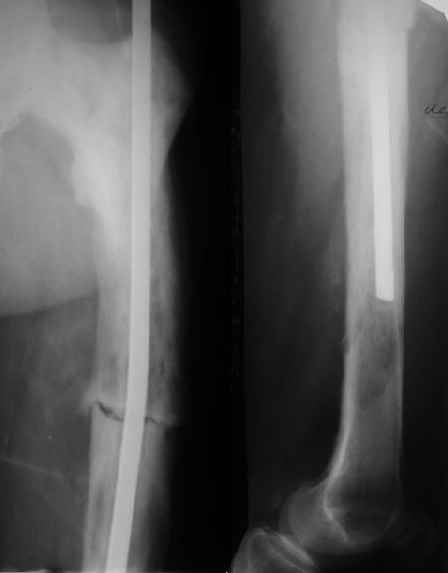

Пациент 82 лет, поступил через 5 мес. с несросшимся переломом после открытого интрамедуллярного остеосинтеза. Выполнили реостеосинтез стержнем 12 мм. ( мах. доступного нам в 2003 г.) Через 4 мес динамизация. В течении 2х лет сращения нет, тем не менее конечность опорна (ходит с тростью). От очередного реостеосинтеза отказались из-за сопутств. патологии.

Еще один пример. Пациентка с юга России, прислала рентгенограммы через год. На сегодня прошло 2 г. 8 мес. после операции. Несмотря на не очень убедительный процесс сращения, пациентка ходит. Учитывая остеопороз при Педжете, решили, что динамизировать вообще не нужно.

При переломах на фоне болезни Педжета металлоконструкция часто служит эндопротезом, несущим нагрузку. Динамизация индивидуальна,- по рентген-динамике. Основной упор- на медикаментозную терапию- см. канд. дисс. Колондаева А.Ф.

Стержень можно было бы поставить подлиннее.